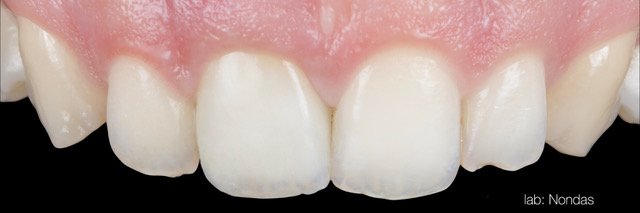

• Single implants in the esthetic zone.

• The importance of implant design, implant connection, abutment selection and treatment workflow.

• How to understand and develop the transmucosal contour around implants.